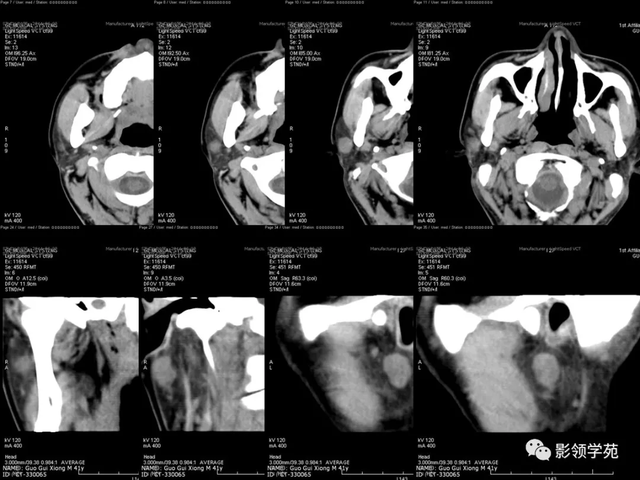

病例1:男性, 41岁,因“发现右耳垂下肿物1月余”:

病理:混淆瘤

病例2:女,30岁,发现右耳垂下肿物9月